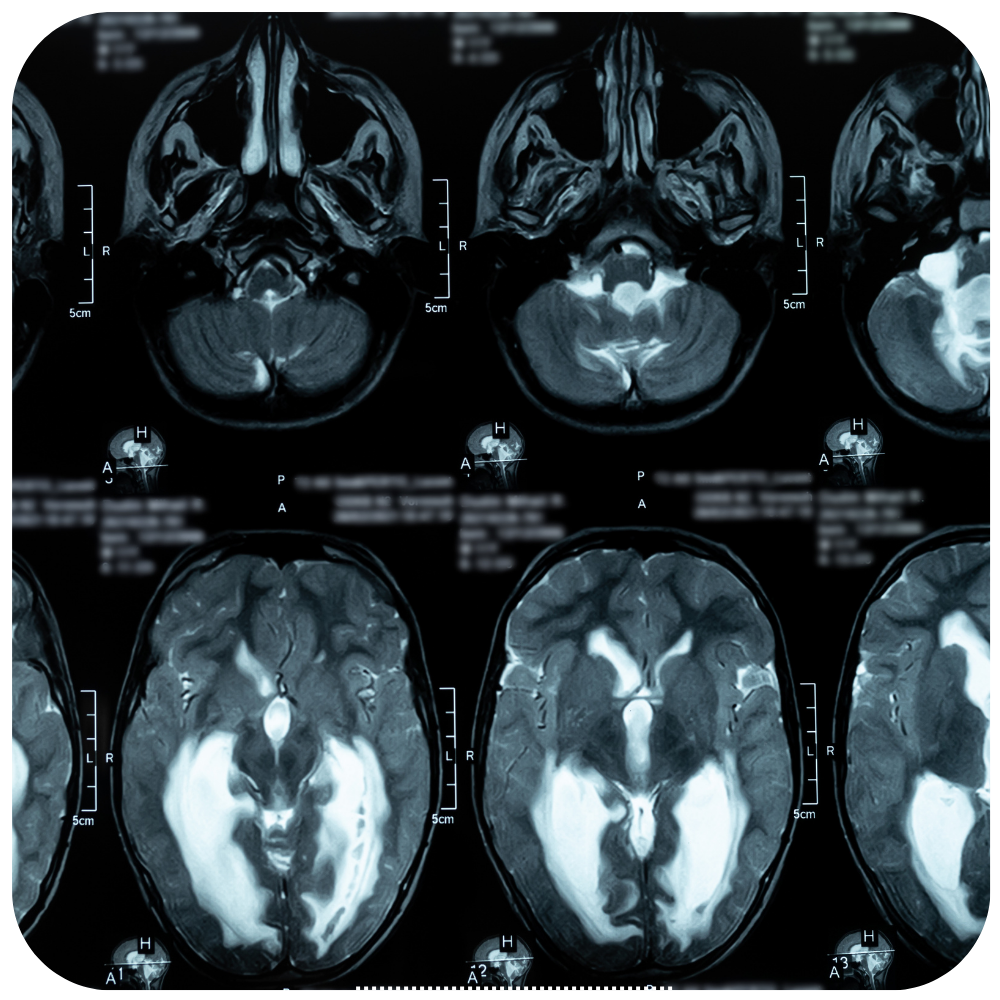

Hidrocefalia es la acumulacion de liquido cefalorraquideo dentro del sistema nervioso y que se caracteriza por dolor de cabeza, náusea, vómito, visión borrosa y somnolencia; lo cual se trata mediante la colocación de una válvula ventrículo peritoneal.